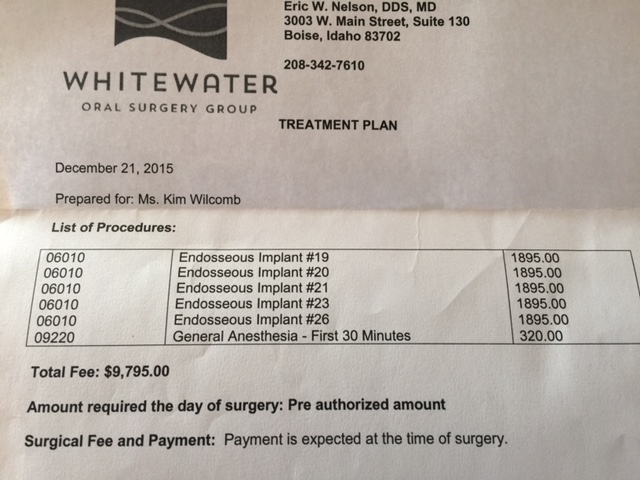

In anticipation of the second tumor, Kim is still needing to address the reconstruction of the removal of the original tumor. At this stage, one-year post surgery, the plan is to begin the preparation for porcelain implants, or a new set of teeth. In order to do this, Kim will face a third surgery in which five metal posts will be implanted into the graphed bone in her jaw. This surgery cost is roughly $9,795. However, the quote only includes 30 minutes of general anesthesia, and the doctors anticipate surgery could take up to an hour and a half.

In anticipation of the second tumor, Kim is still needing to address the reconstruction of the removal of the original tumor. At this stage, one-year post surgery, the plan is to begin the preparation for porcelain implants, or a new set of teeth. In order to do this, Kim will face a third surgery in which five metal posts will be implanted into the graphed bone in her jaw. This surgery cost is roughly $9,795. However, the quote only includes 30 minutes of general anesthesia, and the doctors anticipate surgery could take up to an hour and a half.